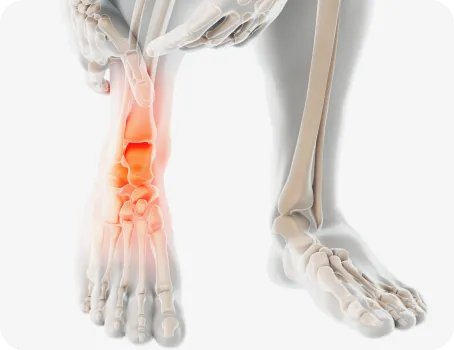

발목터널증후군

발목 안쪽 복사뼈와 발뒤꿈치를 잇는 굽힘근지지띠의 안쪽 공간을 발목터널이라고 합니다.

이 부위가 다양한 원인에 의해 좁아지게 되면, 신경을 압박하게 되는데 이때 감각이 둔해지거나 전기가 통하는 듯 느끼는 증상입니다.

원인

• 기능성평발

• 발목의 잦은 염좌

• 골절

• 타박상에 의한 손상

• 발목의 신경을 압박하는 종양이나 낭종

• 과체중과 비만